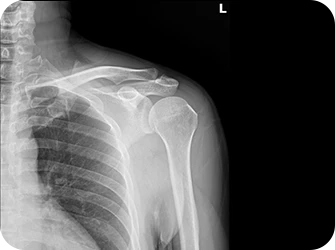

회전근개파열

어깨와 팔을 연결하여 어깨 관절의 회전 운동을 담당하는 근육중 일부가 파열되어 팔과 어깨 통증을 발생시키는 질환으로, 중년층에게 주로 발생되며 무리한 운동으로 인한 30~40대에도 나타납니다.

원인

• 어깨를 장시간 사용할 경우

• 노화로 인한 퇴행성 변화가 있는 경우

• 어깨에 무리가 가는 운동을 한 경우

• 어깨 힘줄 사이의 염증 변화가 있는 경우

• 발육부전, 선천적 이상이 생긴 경우

• 심각한 외상에 의한 경우